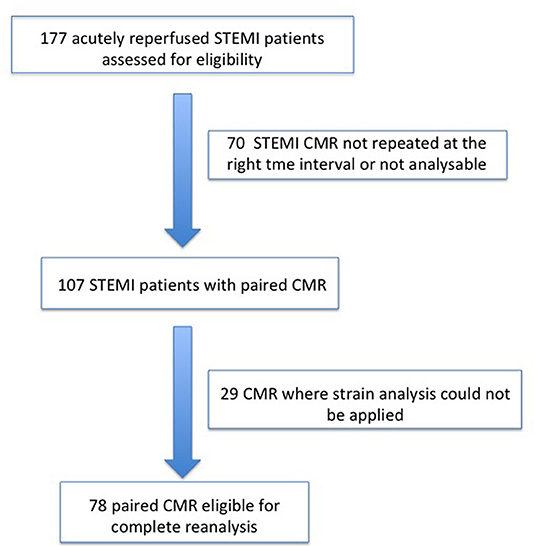

From 2010 to 2019, a total of 1,285 STEMI patients underwent pPCI in Policlinico Umberto I Hospital, of which ~15% had CMR performed and 78 were recruited as reported in the flow chart (Figure 1). According to our internal procedures, when allowed by the clinical condition of the patient, the availability of the scanner/staff, and in the absence of contraindications, CMR was performed in reperfused STEMI patients for the assessment of post-infarction myocardial injury during the acute phase and to detect complications at short and long term follow up. Among the study population of enrolled STEMI patients, 38 (49%) showed adverse, 22 (28%) reverse, and 18 (23%) null LV remodeling, assessed by paired CMR exams (baseline and FU-CMR). Demographic, clinical, angiographic, and pharmacological characteristics of the STEMI population according to the three groups are illustrated in Table 1. No differences in demographic data, cardiovascular risk factors, angiographic presentation, or laboratory findings were found. Agreement in strain measurements was excellent with ICC between 0.922 and 0.943 (p < 0.001, Supplementary Material) and p > 0.43 (range 0.43–0.85) at Wilcoxon's test. Regarding pharmacological therapy, no differences were noted about beta-blocker, antidiabetics, statins, ACE-inhibitors, spironolactone, GbIIb-IIIa inhibitors, and clopidogrel use among the three LV remodeling categories, except for the pre-pPCI ASA administration. At the first CMR exam, patients with LV adverse remodeling showed higher AAR, IS, and MVO, if compared to the other two groups (Table 2). Meanwhile, at FU-CMR, the adverse remodeling group had lower LVEF, greater IS extent, and lower LV-RI. At CMR strain analysis, significantly worse GCS and GLS values at baseline and FU-CMRs in the adverse LV remodeling group, compared to the sum of the other two groups, were found (Figure 2, Table 2). After adjusting for age, sex, BMI by ANCOVA analysis, the only CMR derived parameters that reported a different statistical significance if compared with ANOVA analysis, according to the three remodeling groups, were baseline AAR, baseline MVO, FU IS, baseline GRS, and baseline GLS.

Figure 1. Recruitment flow chart. STEMI, ST-elevation myocardial infarction; CMR, Cardiac magnetic resonance.